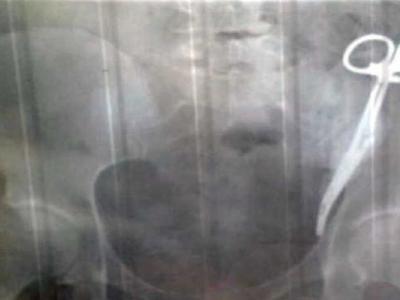

خاتون کے پیٹ میں سرجیکل قینچی 23 سال تک موجود رہی